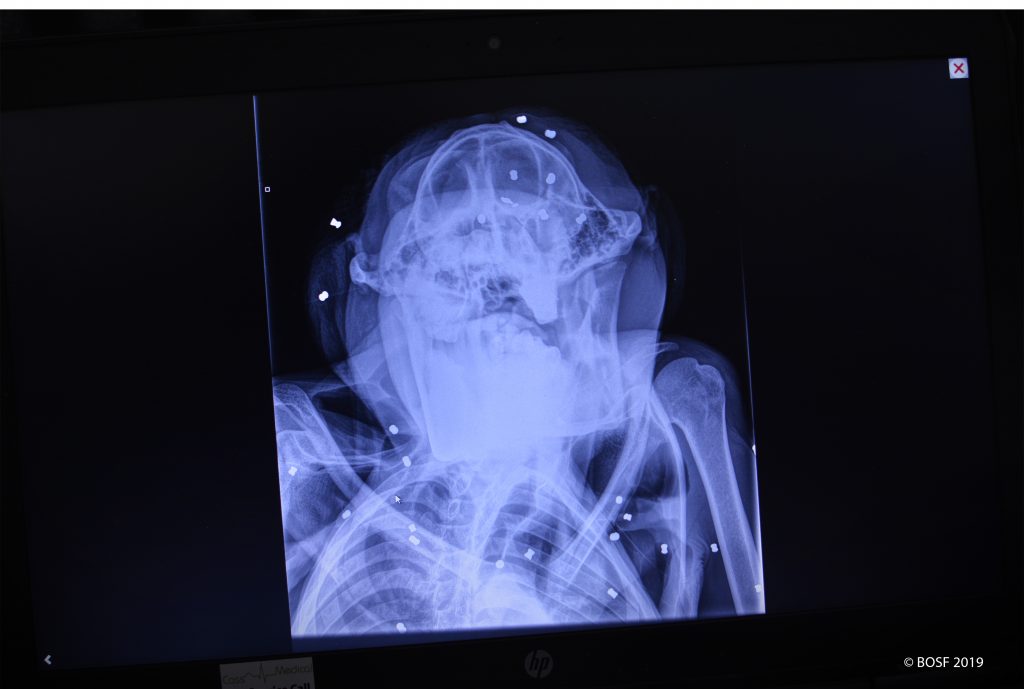

Treatment commenced immediately and in addition to severe malnutrition, dehydration and parasites, palpitations of his body revealed several bullets lodged beneath his skin. After doing all that was possible in the field, he was arrived at the Nyaru Menteng Rehabilitation Centre at around 8pm for intensive care.

During further evaluations, x-rays revealed several bullets lodged in Sapat’s body, with no less than 67 pieces of schrapnel. At this moment it has been decided to postpone the surgical removal of the bullets and items, at least until the time that his condition is deemed stable.

Dr. Ir. Jamartin Sihite MSc., BOS Foundation CEO, commented on the rescue; “Rescues such as these are our greatest fear in relation to the forest fires that result from slash-and-burn land clearing. These perilous conditions force wildlife to stray outside of their habitats to save themselves, but this creates conflict with humans. The bullets in Sapat’s body are clear evidence of his escape from such conflict. We implore the Indonesian government to limit the use of air rifles. If treatment goes well and he recovers, we will undoubtedly release him back to a safe, natural forest. But that is a big ‘if’.